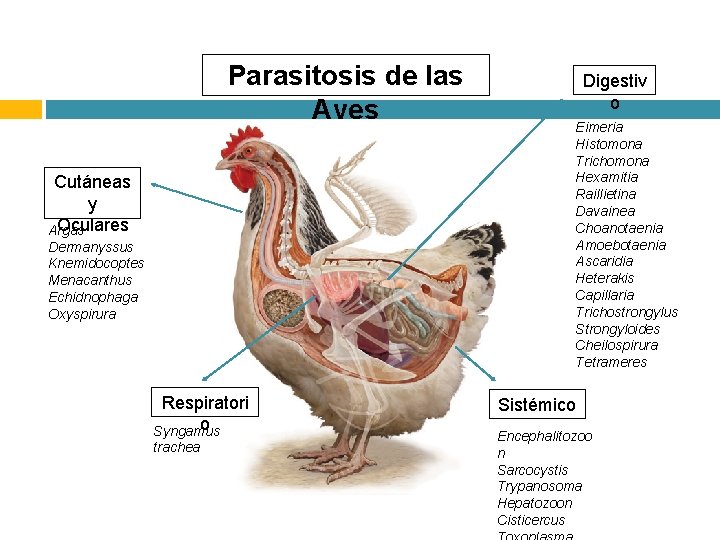

Parasitosis de las Aves Cutáneas y Oculares Argas Dermanyssus Knemidocoptes Menacanthus Echidnophaga Oxyspirura Respiratori o Syngamus trachea Digestiv o Eimeria Histomona Trichomona Hexamitia Raillietina Davainea Choanotaenia Amoebotaenia Ascaridia Heterakis Capillaria Trichostrongylus Strongyloides Cheilospirura Tetrameres Sistémico Encephalitozoo n Sarcocystis Trypanosoma Hepatozoon Cisticercus